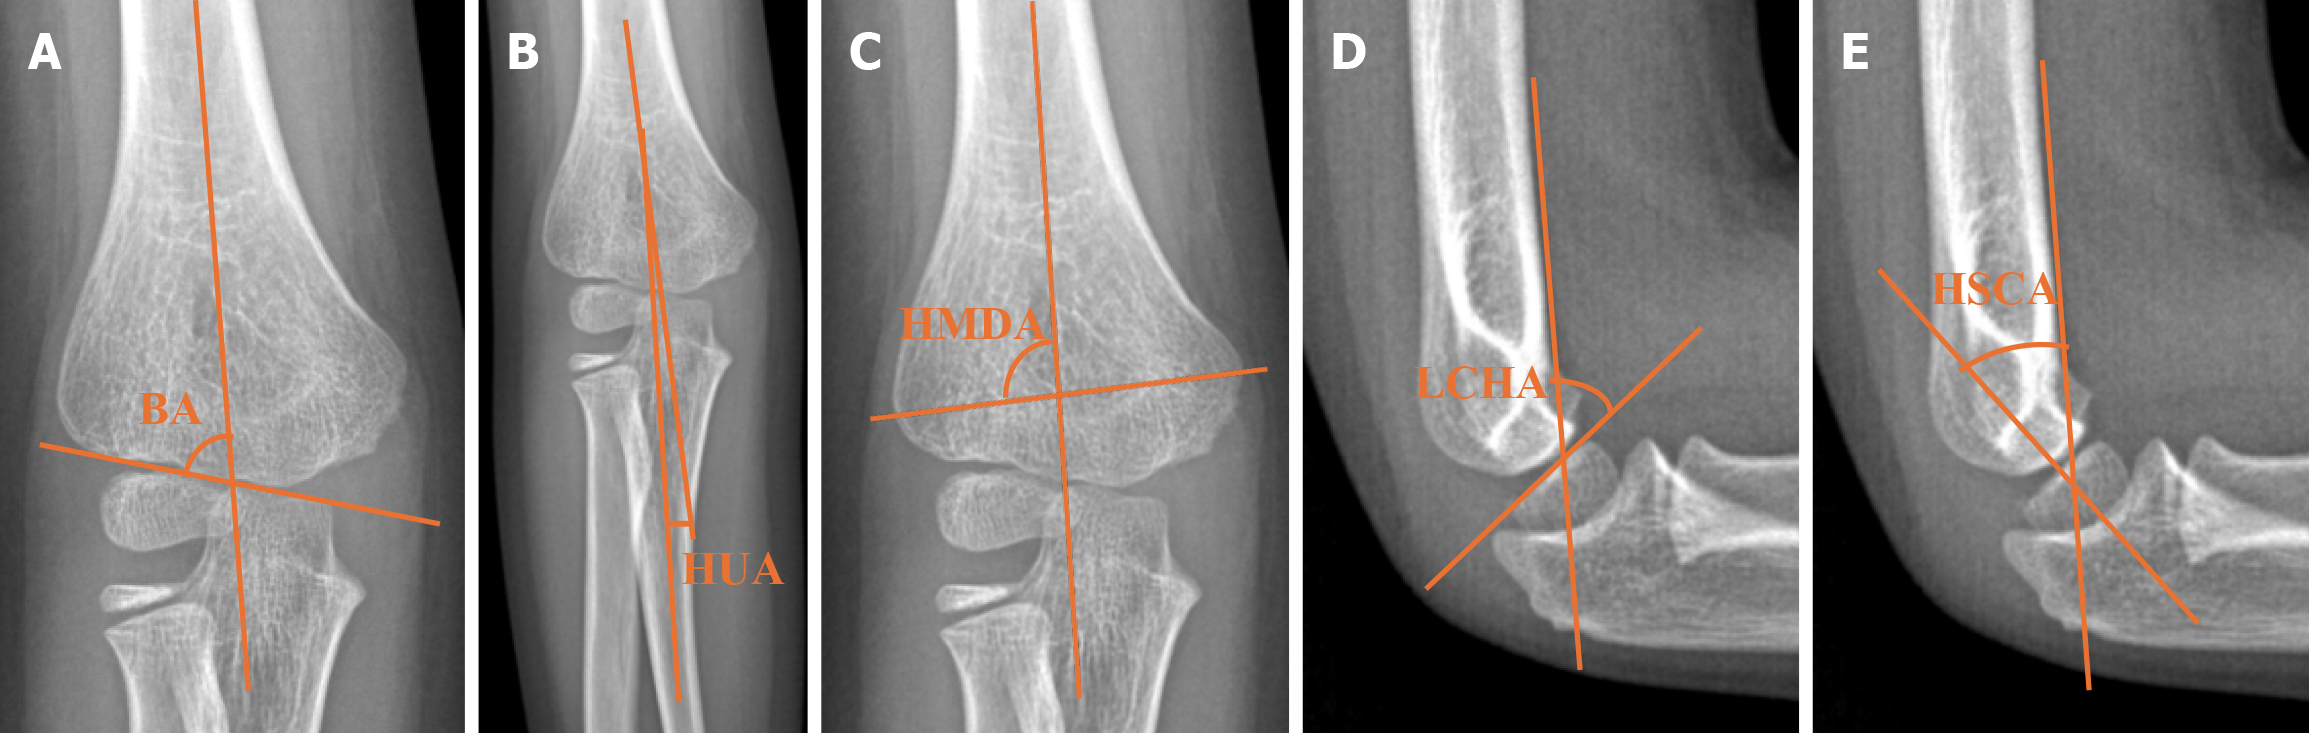

Figure 1 Angular measurements.

A: Baumann angle; B: Humeroulnar angle; C: Humerus metaphysis diaphysis angle; D: Lateral capitellohumeral angle; E: Humerus shaft condyler angle. BA: Baumann angle, HUA: Humeroulnar angle, HMDA: Humerus metaphysis diaphysis angle, LCHA: Lateral capitellohumeral angle, HSCA: Humerus shaft condyler angle.